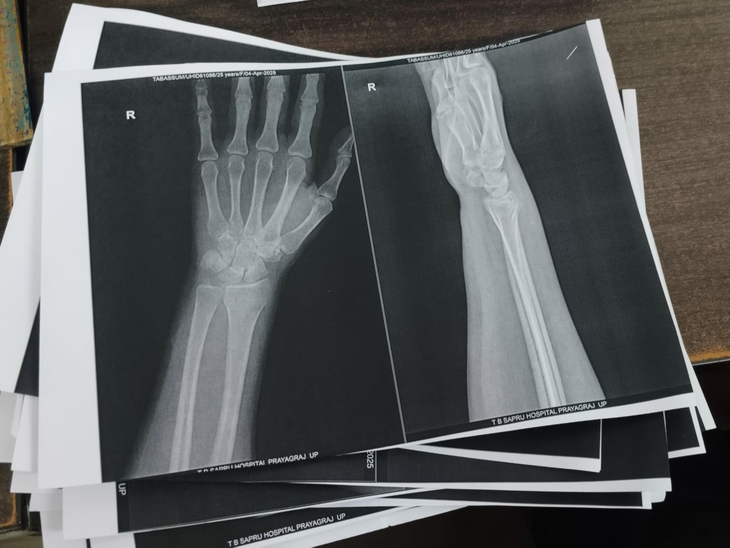

प्रयागराज के तेज बहादुर सप्रू (बेली) हॉस्पिटल में कहने के लिए डिजिटल एक्स-रे तो हो रहा है लेकिन रिपोर्ट उन्हें फिल्म पर नहीं बल्कि ए-4 साइज के सादे पन्ने पर दिया जा रहा है। ऐसे में इस डिजिटल एक्स-रे होने का फायदा क्या है। मरीज 2 से 3 घंटे तक इंतजार क

पन्ने पर रिपोर्ट लेकर डॉक्टर के पास जाता है तो पता चलता है कि हड्डी या नस में क्या दिक्कत है यह तो स्पष्ट नहीं हो पा रहा है। फिर मजबूरन मरीज को बाहर जाकर प्राइवेट सेंटर पर एक्स-रे कराना पड़ता है।

इस तरह ए-4 साइज के कागज पर दिया जा रहा है रिपोर्ट।

यदि कोई मरीज एक्स-रे कक्ष के कर्मचारियों से फिल्म पर रिपोर्ट मांगता है तो बताया जाता है कि CMS मैडम से आदेश कराएं तभी फिल्म मिल पाएगा। यहां प्रतिदिन 200 से ज्यादा एक्सरे होता है लेकिन फिल्म सिर्फ 8 से 10 लोगों को ही दिया जाता है। बाकी लोग पन्ने पर रिपोर्ट लेकर टहलते रहते हैं।